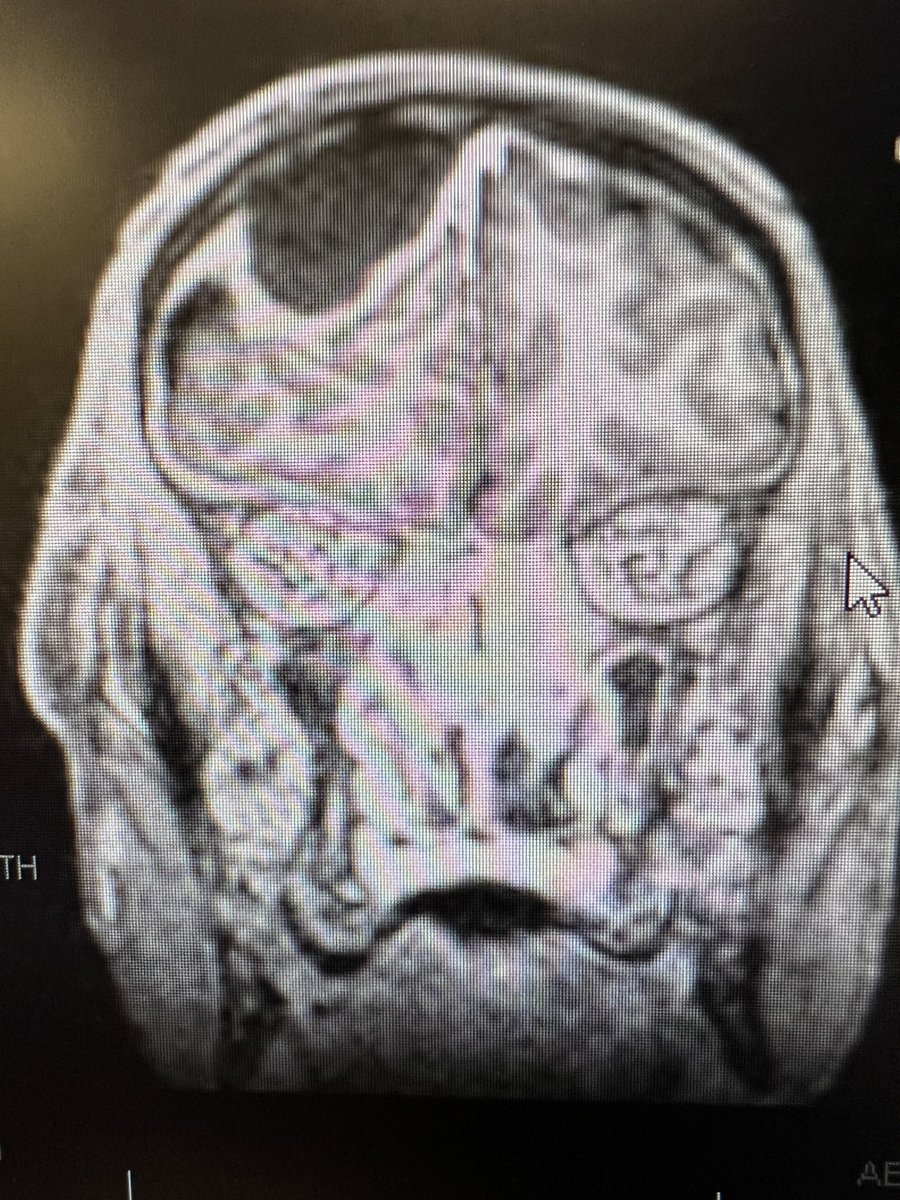

Just sharing the link to my case submission on MACS that is now available on the Cushing’s Hub website as an interactive case study. cushingshub.com/case-studies/a… @springermeded #Endotwitter